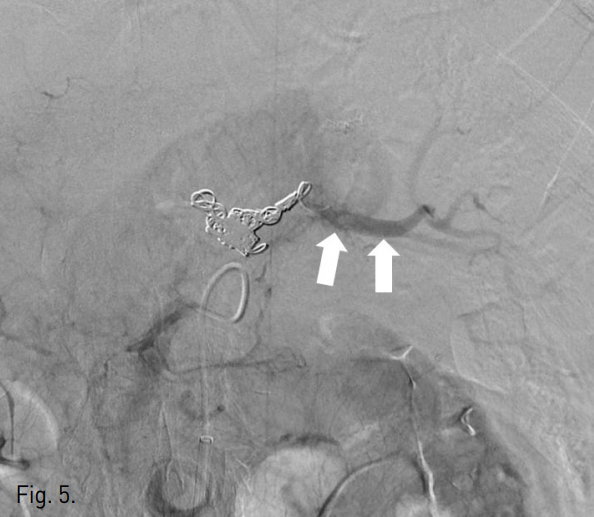

복강동맥조영술에서 비장동맥 근위부에 좌위동맥 잔류부(left gastric artery stump)가 보였으며, 그 끝에서 발생한 가성동맥류가 있다(Fig. 2). 비장동맥에 stent-graft 삽입을 위하여 우측 총대퇴동맥을 통해 8F 65cm long sheath(Teleflex, 회사, USA)를 삽입하였다. Sheath의 tip을 비장동맥 근위부까지 진입시키고 Amplatz stiff guidewire(Cook, USA)를 비장동맥 원위부까지 통과시켰다. 이후 10mm × 4cm stent-graft(S&G, Korea)의 진입을 시도하였으나 stent-graft 시스템이 비장동맥 근위부의 급격한 커브를 통과하지 못하였다(Fig. 3). 총간동맥 조영술에서 잔류위를 공급하는 부위동맥(accessory gastric artery)이나 다른 측부순환로는 보이지 않아 비장동맥 색전술을 시행할 경우 위 경색(gastric infarction)이 우려되는 상황이었으나, 수술을 담당하였던 외과의와의 상의 하에 좌위동맥 잔류부를 포함하여 비장동맥을 코일을 이용하여 색전하였다(Fig. 4). 먼저 10mm × 5cm Standard coil(Cook, USA) 2개를 이용하여 frame을 형성하고 이후 8mm × 14cm Nester coil (Cook, USA) 7개를 이용하여 색전술을 시행하였다. 코일 색전술 도중 코일의 일부가 가성동맥류로 돌출하였으나 좌위동맥 잔류부를 중심으로 비장동맥의 원위부부터 근위부까지 색전하였다. 색전술 후 상장간막동맥조영술에서 미세한 측부순환로를 통해 원위부 비장동맥이 매우 약하게 조영됨을 확인하였다(Fig. 5). 시술 후 12시간에 시행한 CT 조영증강 전영상에서 위벽에 전날 시술시 사용한 조영제가 남아 있는 소견이 보여 잔류위의 관류가 매우 저하되어 있음을 알 수 있었고(Fig. 6a) 비장의 조영증강도 매우 저하되어 있었다. 그러나 동맥기 영상에서 원위부 비장동맥은 조영이 되어 보였다. 시술 7일후 시행한 CT상에서는 위점막의 조영증강은 정상적으로 보였고, 비장에도 다발성의 작은 경색 소견이 보였으나 전반적인 조영증강은 회복된 양상이었다(Fig. 6b). 환자는 시술 52일 후 정상 식이 가능한 상태로 퇴원하였다.

Fig. 5

Post-embolic superior mesenteric arteriogram shows faint blood flow in distal splenic artery (arrows) by collateral supply.